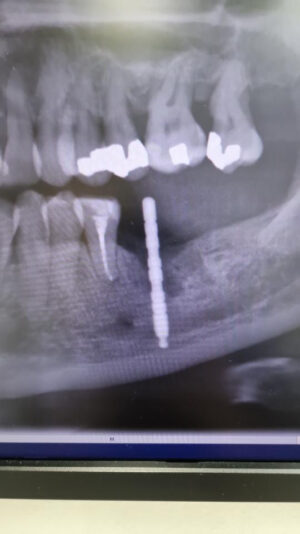

• Sorry if this is a double post. I was wondering if this case should be better splinted or with separate crowns. I did look at the research and it seems splinted crowns are better. But I’m just worried as there is already bone loss around the mesial implant would it be better to do separate crowns so she can clean it better

• Hey Chris, thanks for your post! I would leave these UNsplinted. Here’s why:

There is already some bone loss at those implant sites and if you splint those, the situation can get worse as the patient wont be able to clean them as effectively. (What you said)

I can’t think of a benefit to splinting them in this case.